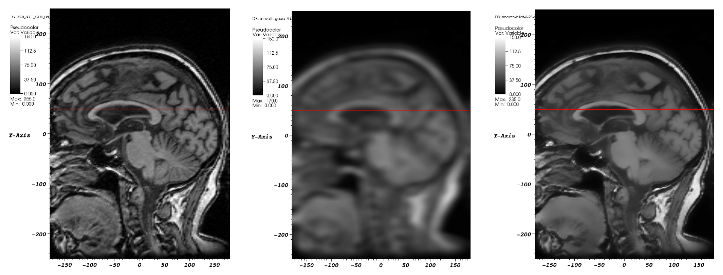

3D GPU Schärfefilter für Computertomographische Daten.

Quelle: